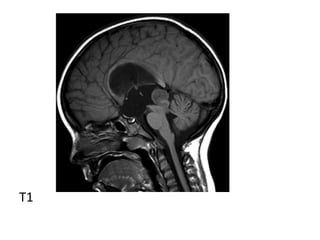

T1

*T1 :

-Iso to slightly hypointense to grey matter